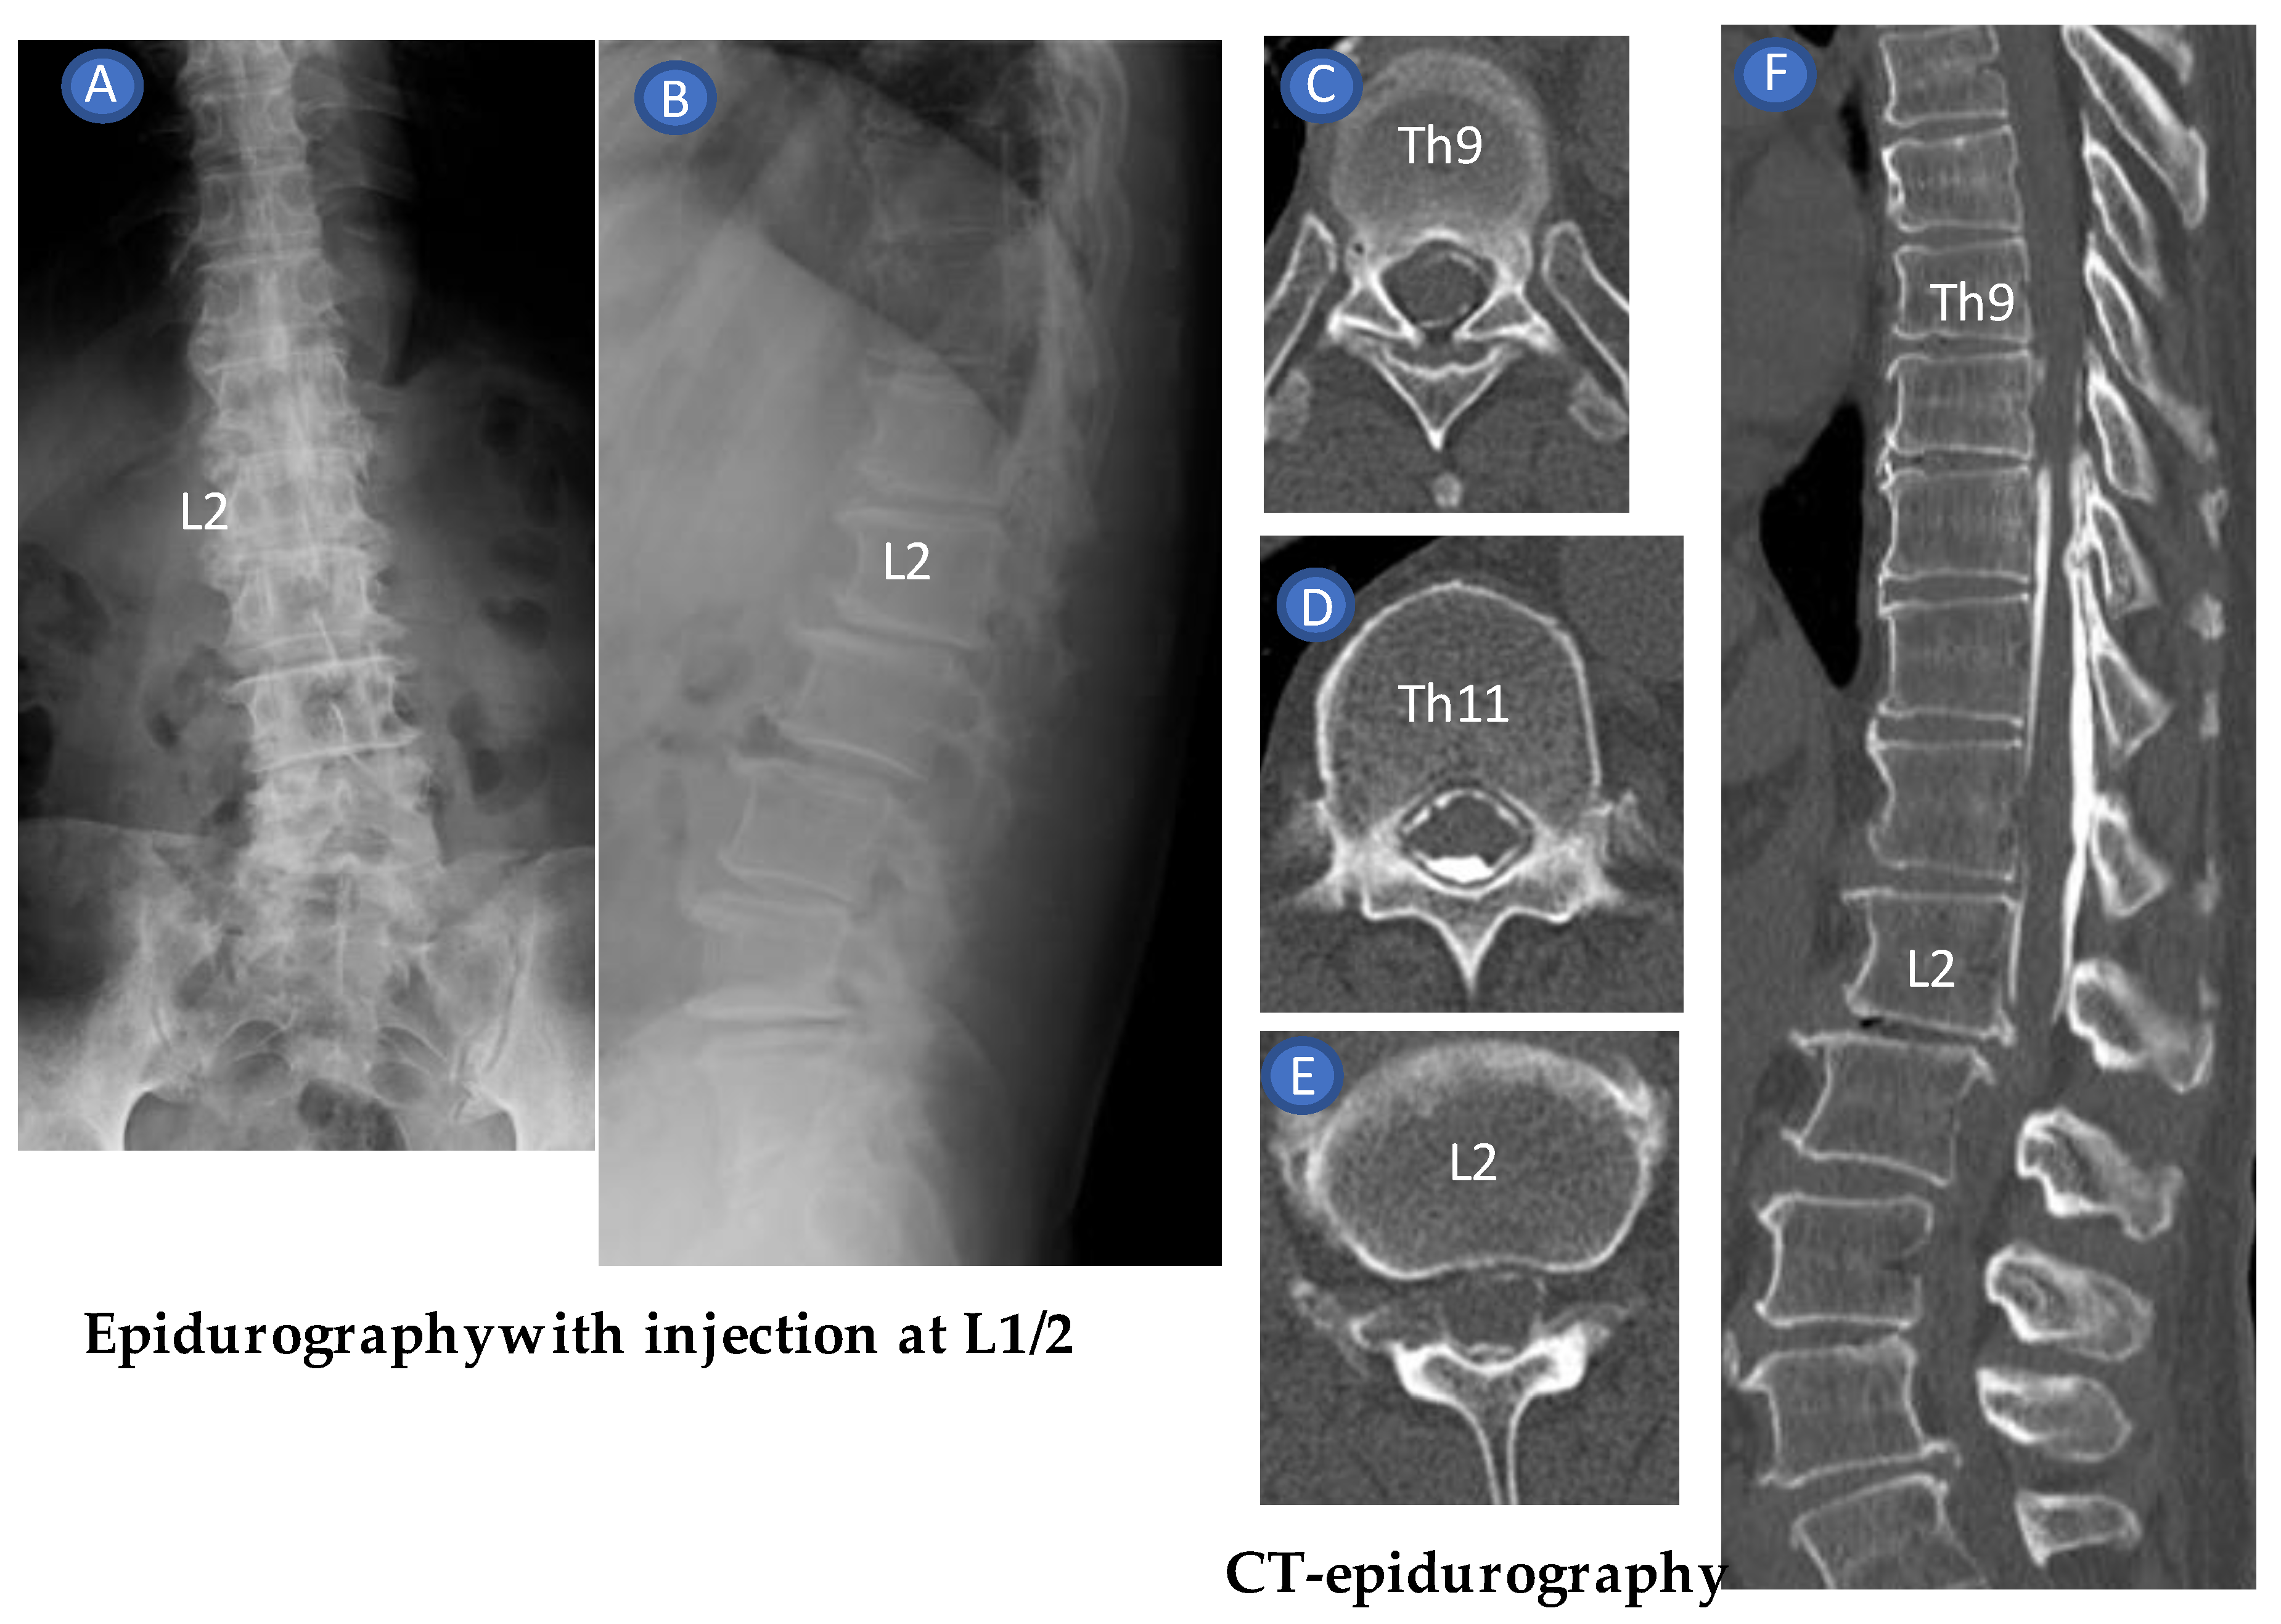

4.1. Measurement of Epidural Space Depth and the Proper Needle Angle (Needle Guide)

4.2. US-Guided Techniques